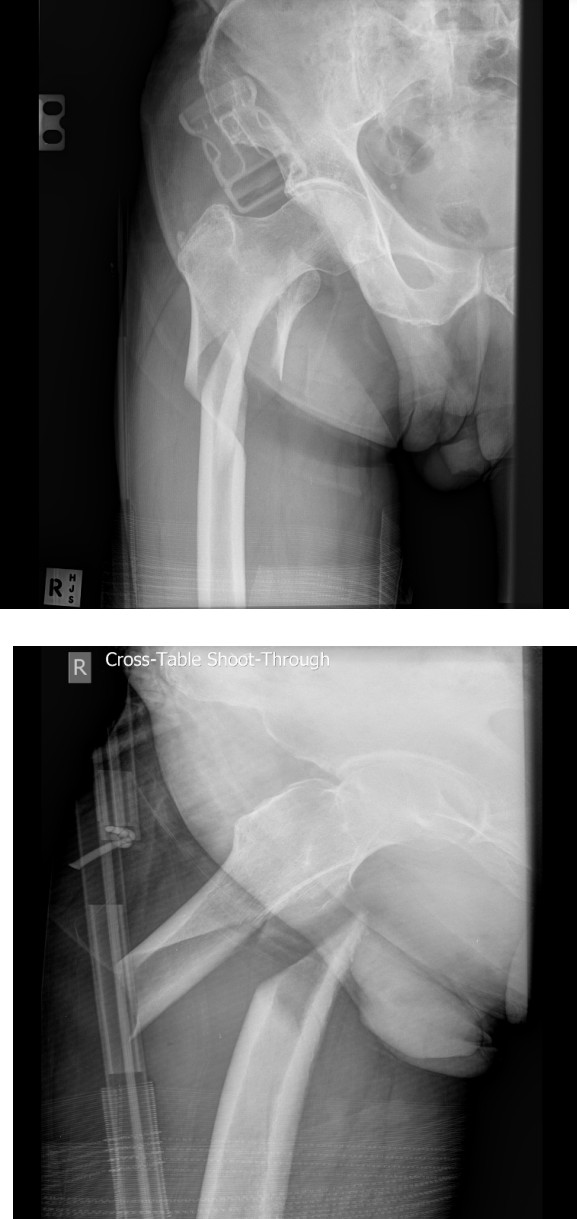

Pelvic crush injury

A 22-year-old Ubereats delivery man is brought in by retrieval to your tertiary ED having been run over by a …